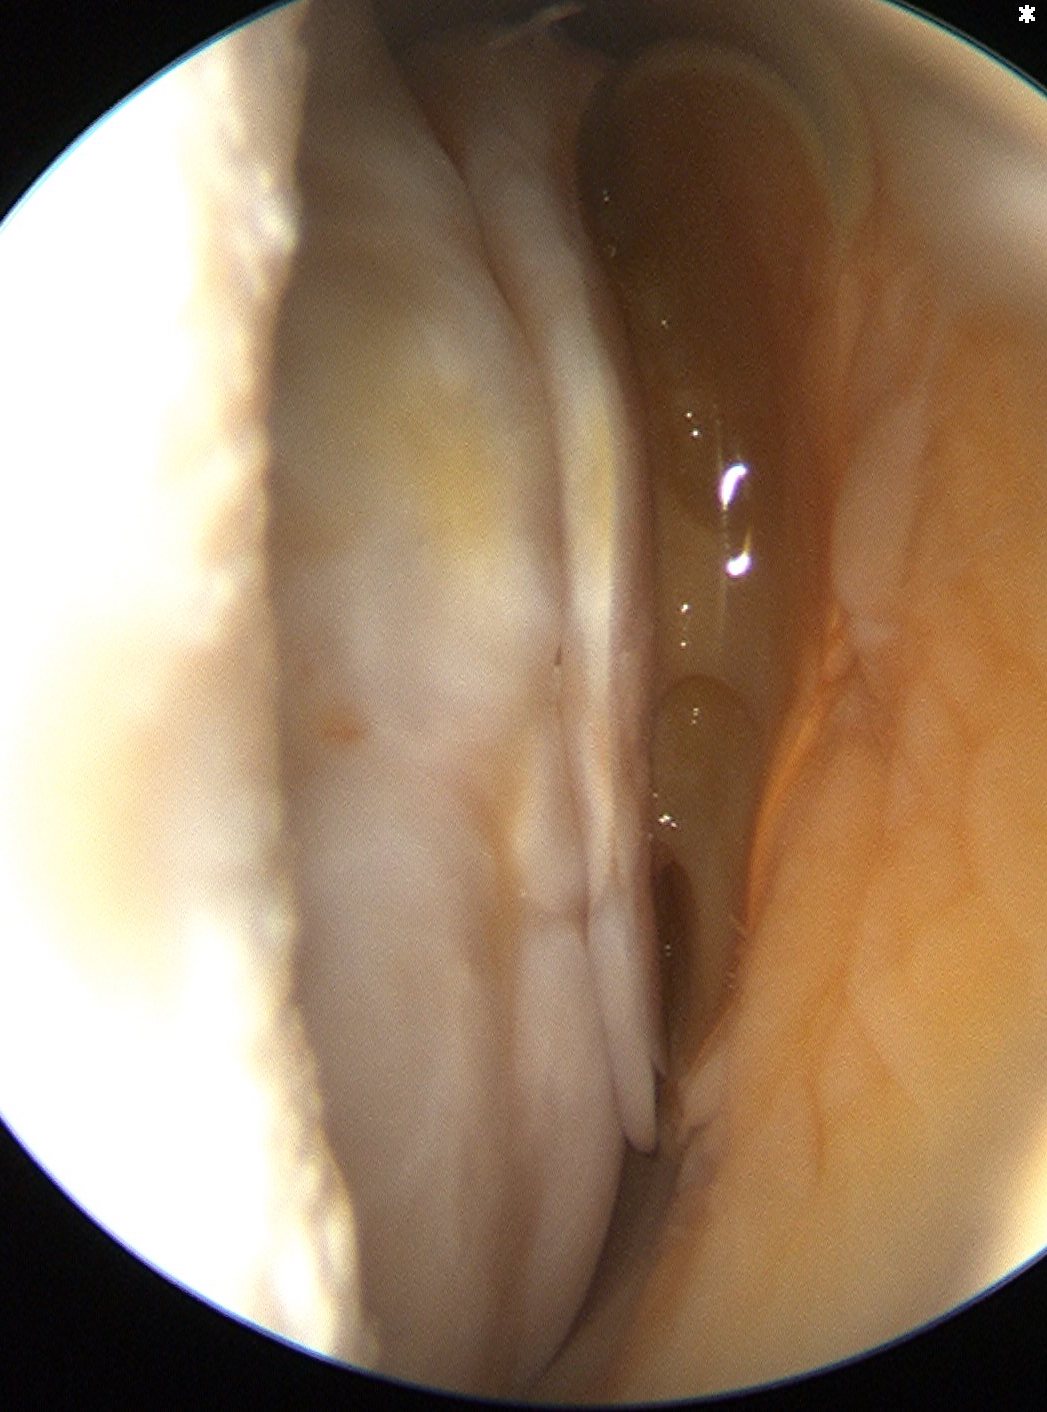

Glenohumeral joint assessment

Labrum

Anterior inferior labral tears |

SLAP tears | Posterior labral tears |

Below equator 3 - 6 o'clock |